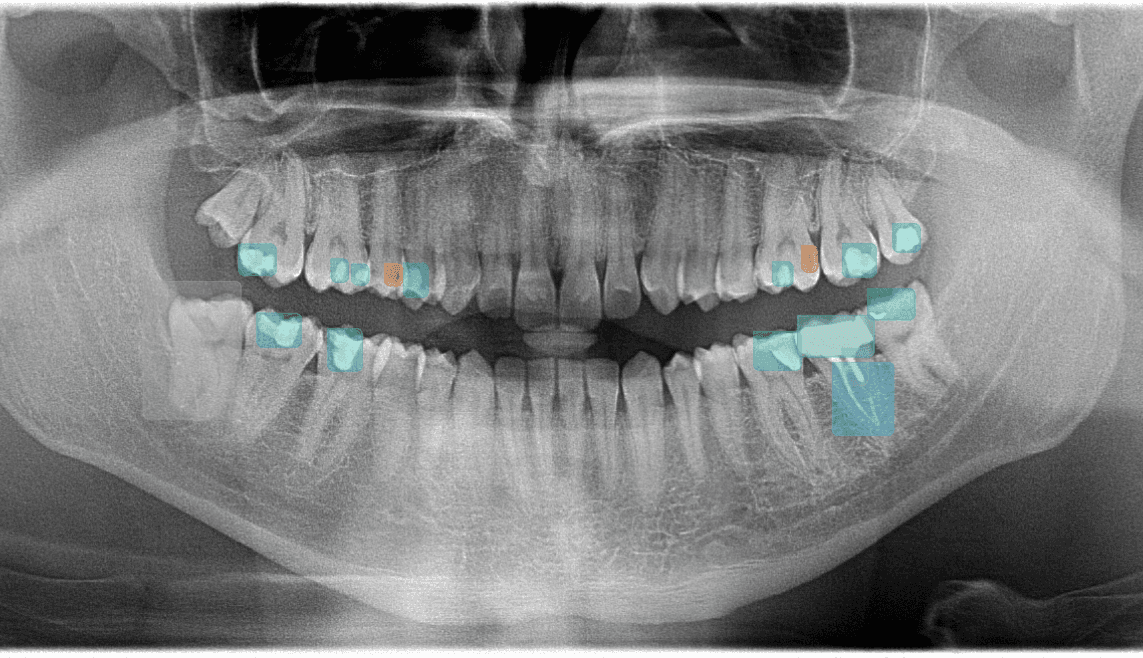

Anatomy marker

Bone segmentation

Panoramic (OPG)Bone levels, impacted teeth, sinuses, and broad candidate-observation review across all quadrants

01Anatomy DetectionMay mark IAN canal, mental foramen, maxillary sinus boundaries, and root apices for clinician review

02Bone SegmentationMay support clinician review of bone levels and possible horizontal or vertical defect patterns

04Teeth Detection & FDIMay number visible teeth using FDI notation (11-48) and associate candidate observations with positions